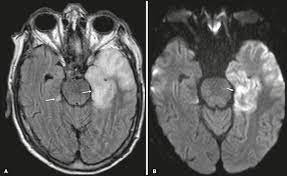

Herpes simplex (hsv) encephalitis is the most common cause of fatal sporadic fulminant necrotizing viral encephalitis and has characteristic imaging findings. Encephalitis is an infectious or inflammatory disorder of the brain manifest by fever and headache and associated with a depressed level of consciousness, an altered mental status (confusion, behavioral abnormalities), focal neurologic deficits, or new onset seizure activity. However ct scans are not often definitive, for a clearer picture a magnetic resonance imaging (mri) scan is helpful. The above described radiological findings are impressive of herpes simplex encephalitis. Mri is the preferred imaging modality for hsv encephalitis.

Herpes simplex (hsv) encephalitis is the most common cause of fatal sporadic fulminant necrotizing viral encephalitis and has characteristic imaging findings. In some cases, advanced imaging techniques such as computed tomography and magnetic resonance imaging (mri) can maertzdorf j, et al. Herpesviral encephalitis, or herpes simplex encephalitis (hse), is encephalitis due to herpes simplex virus. Mushroom sign of pyloric stenosis. The imaging findings of hsv encephalitis on ct may be initially normal or subtly abnormal. Brain ct scan must be urgently performed to rule out a brain lesion with mass effect that would contraindicate lumbar puncture. Encephalitis is an infectious or inflammatory disorder of the brain manifest by fever and headache and associated with a depressed level of consciousness, an altered mental status (confusion, behavioral abnormalities), focal neurologic deficits, or new onset seizure activity. Herpes simplex encephalitis (hse) is the most common cause of fatal sporadic encephalitis worldwide.

Herpes simplex encephalitis is a type of infectious encephalitis which happens when herpes simplex virus (hsv) enters the brain. What the radiologist can expect to see prenatally and postnatally. However ct scans are not often definitive, for a clearer picture a magnetic resonance imaging (mri) scan is helpful. The differential diagnoses include limbic encephalitis (paraneoplastic), gliomatosis cerebri, and status epilepticus. Herpes simplex virus 2 (hsv2) is primarily responsible for disseminated neonatal encephalitis although rare cases have been described in elderly, immunocompromised patients. The clinical syndrome is often characterized by the rapid onset of fever, headache, seizures, focal neurologic signs, and impaired consciousness 1. In some cases, advanced imaging techniques such as computed tomography and magnetic resonance imaging (mri) can maertzdorf j, et al. Mri is the diagnostic modality of choice. Hsv encephalitis, herpes simplex encephalitis. Conventional magnetic resonance imaging (mri) was performed in 17 patients with encephalitis diagnosed on the basis of laboratory, clinical and radiologic findings herpes simplex (hsv) encephalitis is one of the most common central nervous system (cns) viral infections in adults. The above described radiological findings are impressive of herpes simplex encephalitis. The images show symmetrical bilateral putaminal vasogenic oedema with mild restriction on diffusion and no bleed. Two subtypes are recognized which differ in demographics, virus, and pattern of involvement.

Herpes simplex encephalitis is a type of infectious encephalitis which happens when herpes simplex virus (hsv) enters the brain hsv encephalitis mri. It is estimated to affect at least 1 in 500,000 individuals per year, and some studies suggest an incidence rate of 5.9 cases per 100,000 live births.